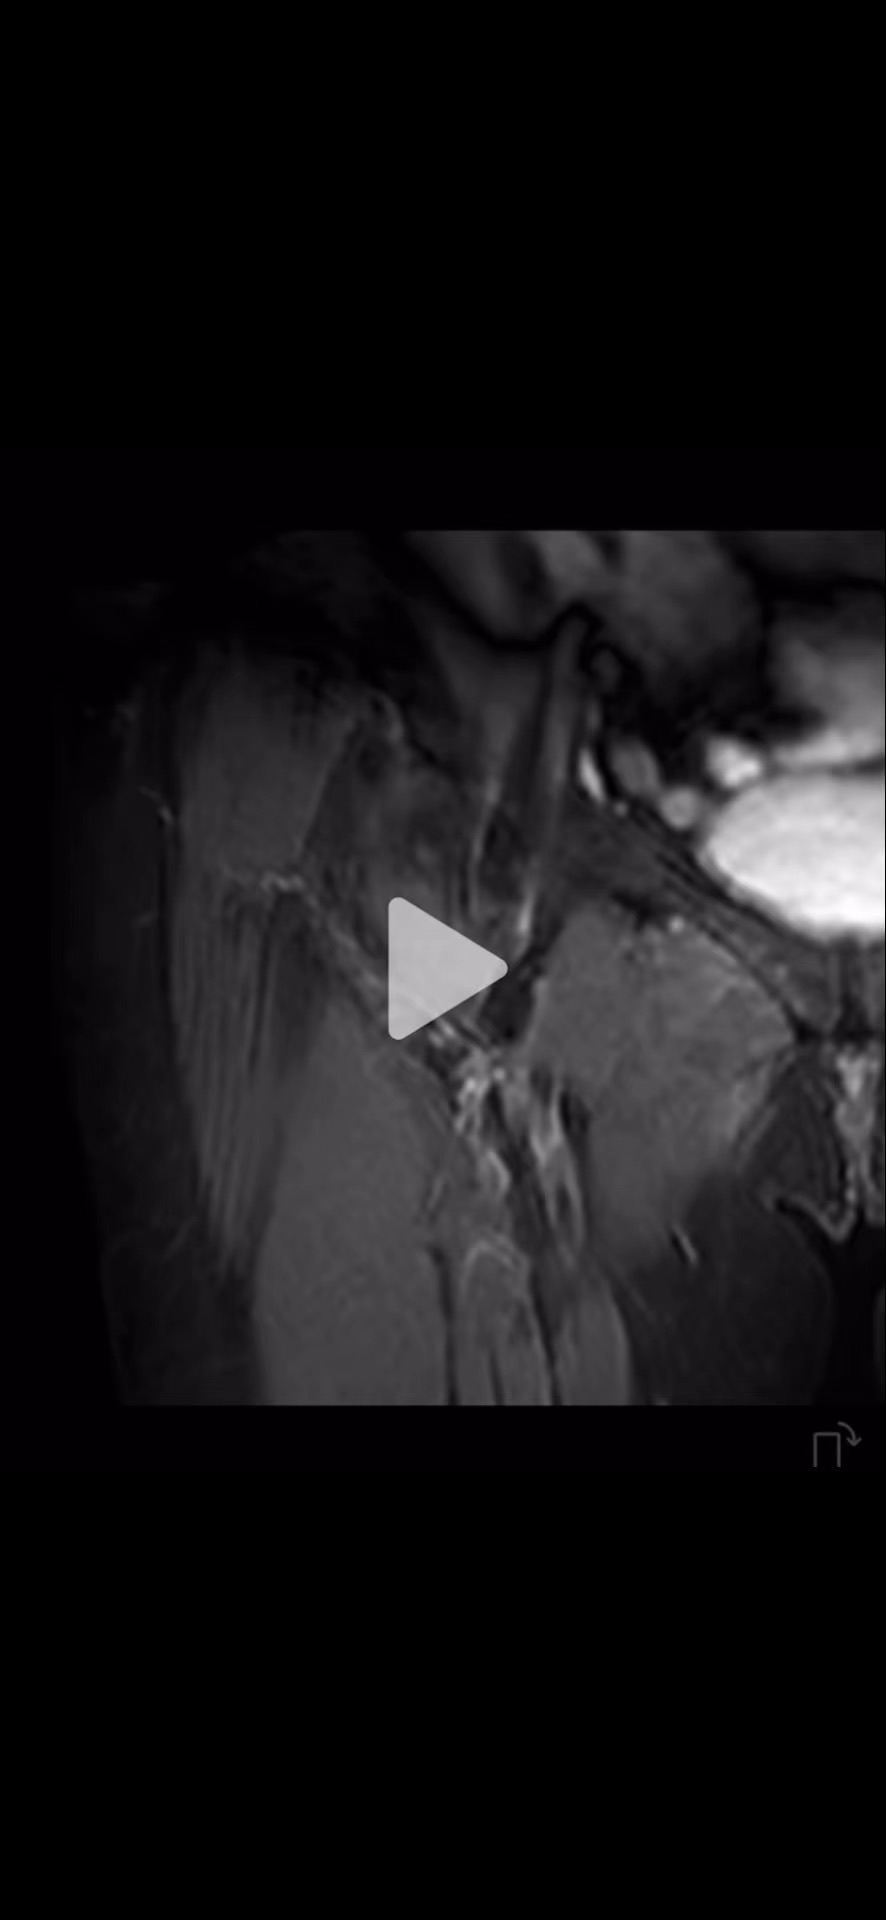

MR: